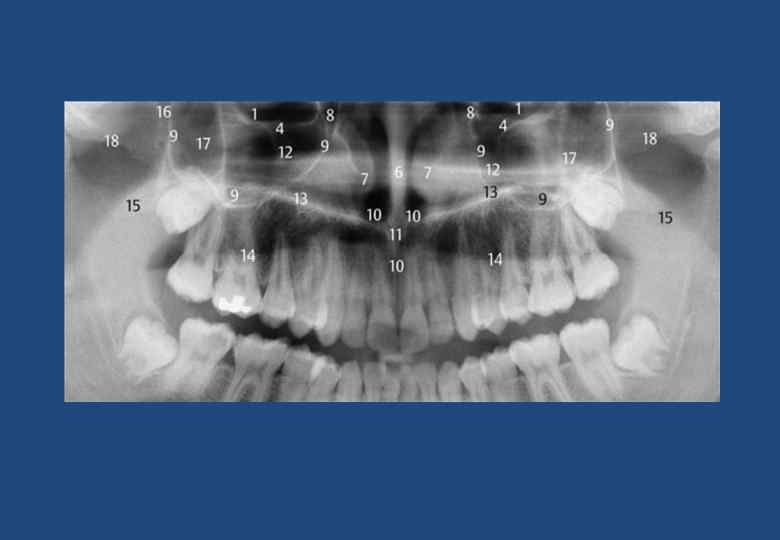

• 1. Рентгенанатомия при ОПТГ. • 2. Глазница • 3. Атлантоокципитальное сочленение • 4. Щека с носогубной складкой • 5. Подглазничный канал • 6. Компактное вещество в основании противоположной стороны челюсти • 7. Перегородка носа с носовым гребнем верхней челюсти • 8. Нижняя носовая раковина • 9. Слезная ямка • 10. Верхнечелюстная пазуха (границы) • 11. Носонебный канал и резцовое отверстие • 12. Верхняя носовая ость • 13. Горизонтальная пластинка небной кости • 14. Латеробазальная граница носовой полости, крыша неба располагается между 12 и 13 • 15. Спинка языка • 16. Небная занавеска • 17. Крыловидно-небная ямка • 18. Тело скуловой кости с безымянной линией • 19. Скуловая дуга